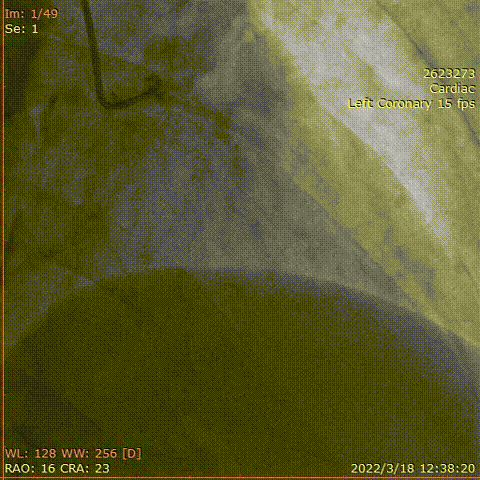

冠脉造影

对右冠脉行介入治疗,钙化较重